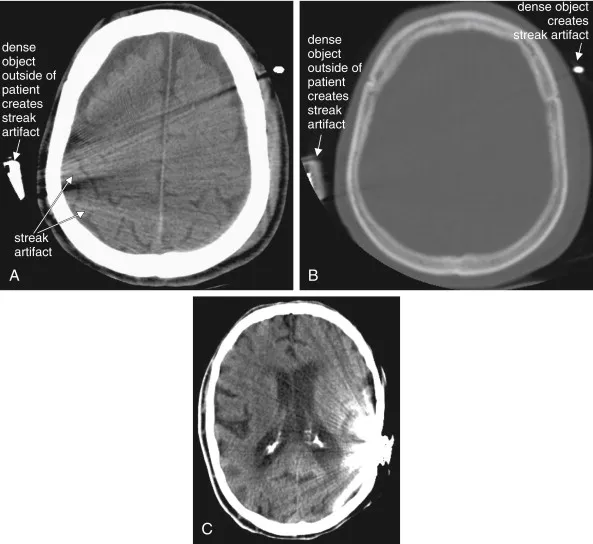

- Common Artifacts:

- Motion: Blurring from patient movement.

- Beam Hardening: Dark streaks between dense objects.

- Metallic Artifact: Severe streaking from implants.